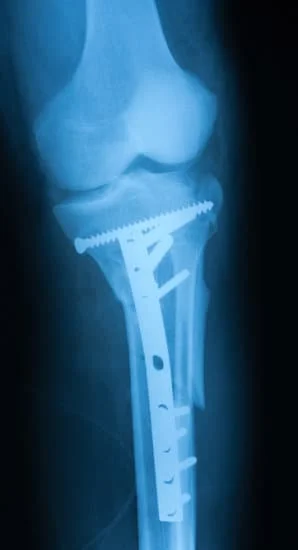

Quality and affordable healthcare has long been the essence in the field of medical sciences & treatment. Every patient expects an early diagnosis and a planned approach to treatment procedures with affordability and access to quality healthcare. Knee replacement, Hip replacement, Fracture treatment are being done by Dr.P.Sankaralingam at very affordable costs without compromising on quality.

• All Trauma & Fracture Fixation (Nails, Plates, Non-union Repairs)